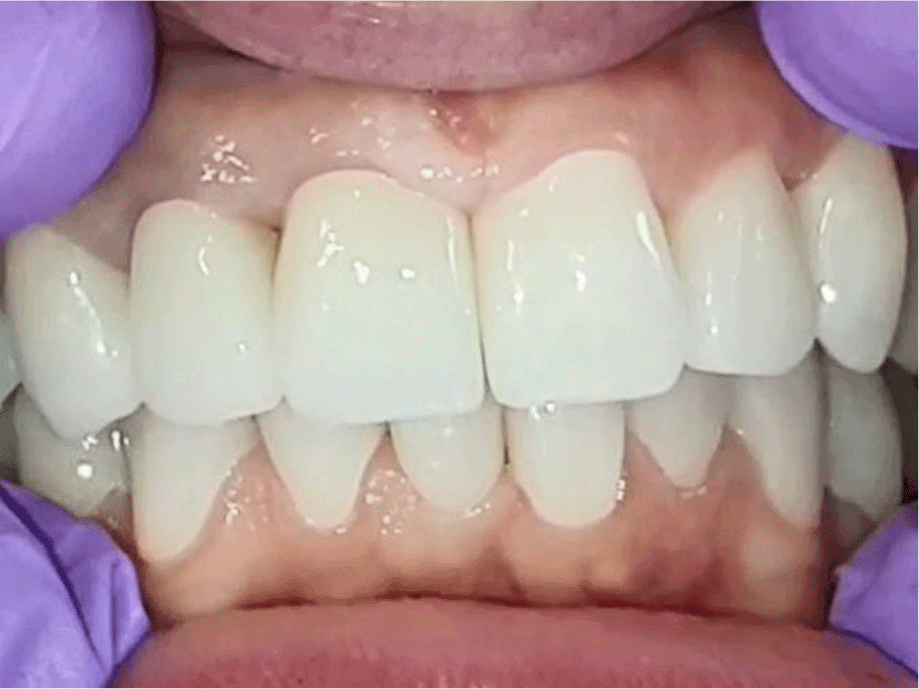

The patient reported a lack of symptoms of TMJ after 3 months, establishing the therapeutic effect of the splint. We then proceeded to the final prosthesis. All constructions were made of ceramics based on zirconium dioxide, with added yttrium and hafnium oxides. The distal defects of the lower jaw were solved with bridge constructions, and single crowns were placed on the frontal teeth (Figures 19 and 20).

26dd931c-41d3-478d-bec1-8cb211d0a4b8_figure19.gif

Figure 19. Zirconia prosthesis on the model.

26dd931c-41d3-478d-bec1-8cb211d0a4b8_figure20.gif

Figure 20. Zirconia prosthesis in the patient’s mouth (try-in procedure).

All of the final constructions were made from Ceramill Zolid FX MultiLayer B2 and Glase (AmannGirrbach). For the upper jaw, single zirconia crowns of the canines and block crowns of 11, 12 and 21, 22, respectively, were made, for the distal defects - bridge restorations of zirconia ceramics. The distal structures of both jaws were cemented first to ensure stable occlusion. Then the crowns were fixed almost at the same time in the frontal section (Figures 21 and 22).

26dd931c-41d3-478d-bec1-8cb211d0a4b8_figure21.gif

Figure 21. Lower zirconia crowns, upper PMMA during the try-in procedure.

26dd931c-41d3-478d-bec1-8cb211d0a4b8_figure22.gif

Figure 22. Upper and lower zirconia crowns.